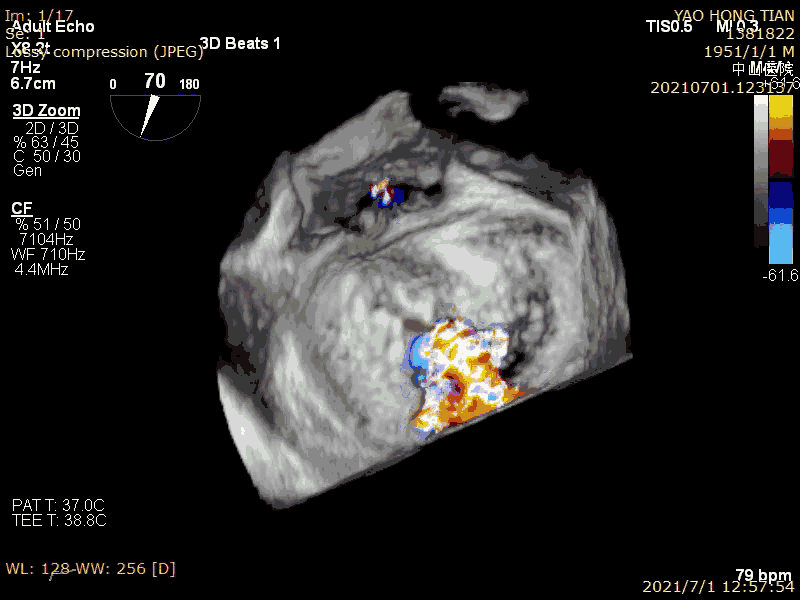

患者,男,70岁。术前超声诊断:左心室射血分数 LVEF 58%,左心室舒张末内径LVDD 52mm,左心房内径LAD 57mm,PASP 63mmHg,二尖瓣瓣尖错位导致重度二尖瓣反流,VC 6*13mm,反流面积19.8cm²(图1-2)。

最后效果(轻微反流),最大/平均压:差4/1mmHg

在二尖瓣反流病因构成中,功能性反流更常见,其为器质性反流的3-4倍(Am Heart J. 2018 ;203:39-48.)。而房性功能性二尖瓣反流(AFMR),在功能性反流里也是非常常见,笔者估测可占到40%。本例结果显示ValveClamp 对AFMR效果良好,操作简便,导管操作时间不到20分钟,总手术时间不到50分钟,术后轻微反流。特别提到的是,本例反流范围达13mm,且反流为多束。一个夹子ValveClamp即起到完美效果,而其他产品很可能需要2-3个夹子,这充分体现了ValveClamp“以小治大” 的设计优点。仅使用单个夹子,可以降低手术难度和手术时间,降低耗材成本。